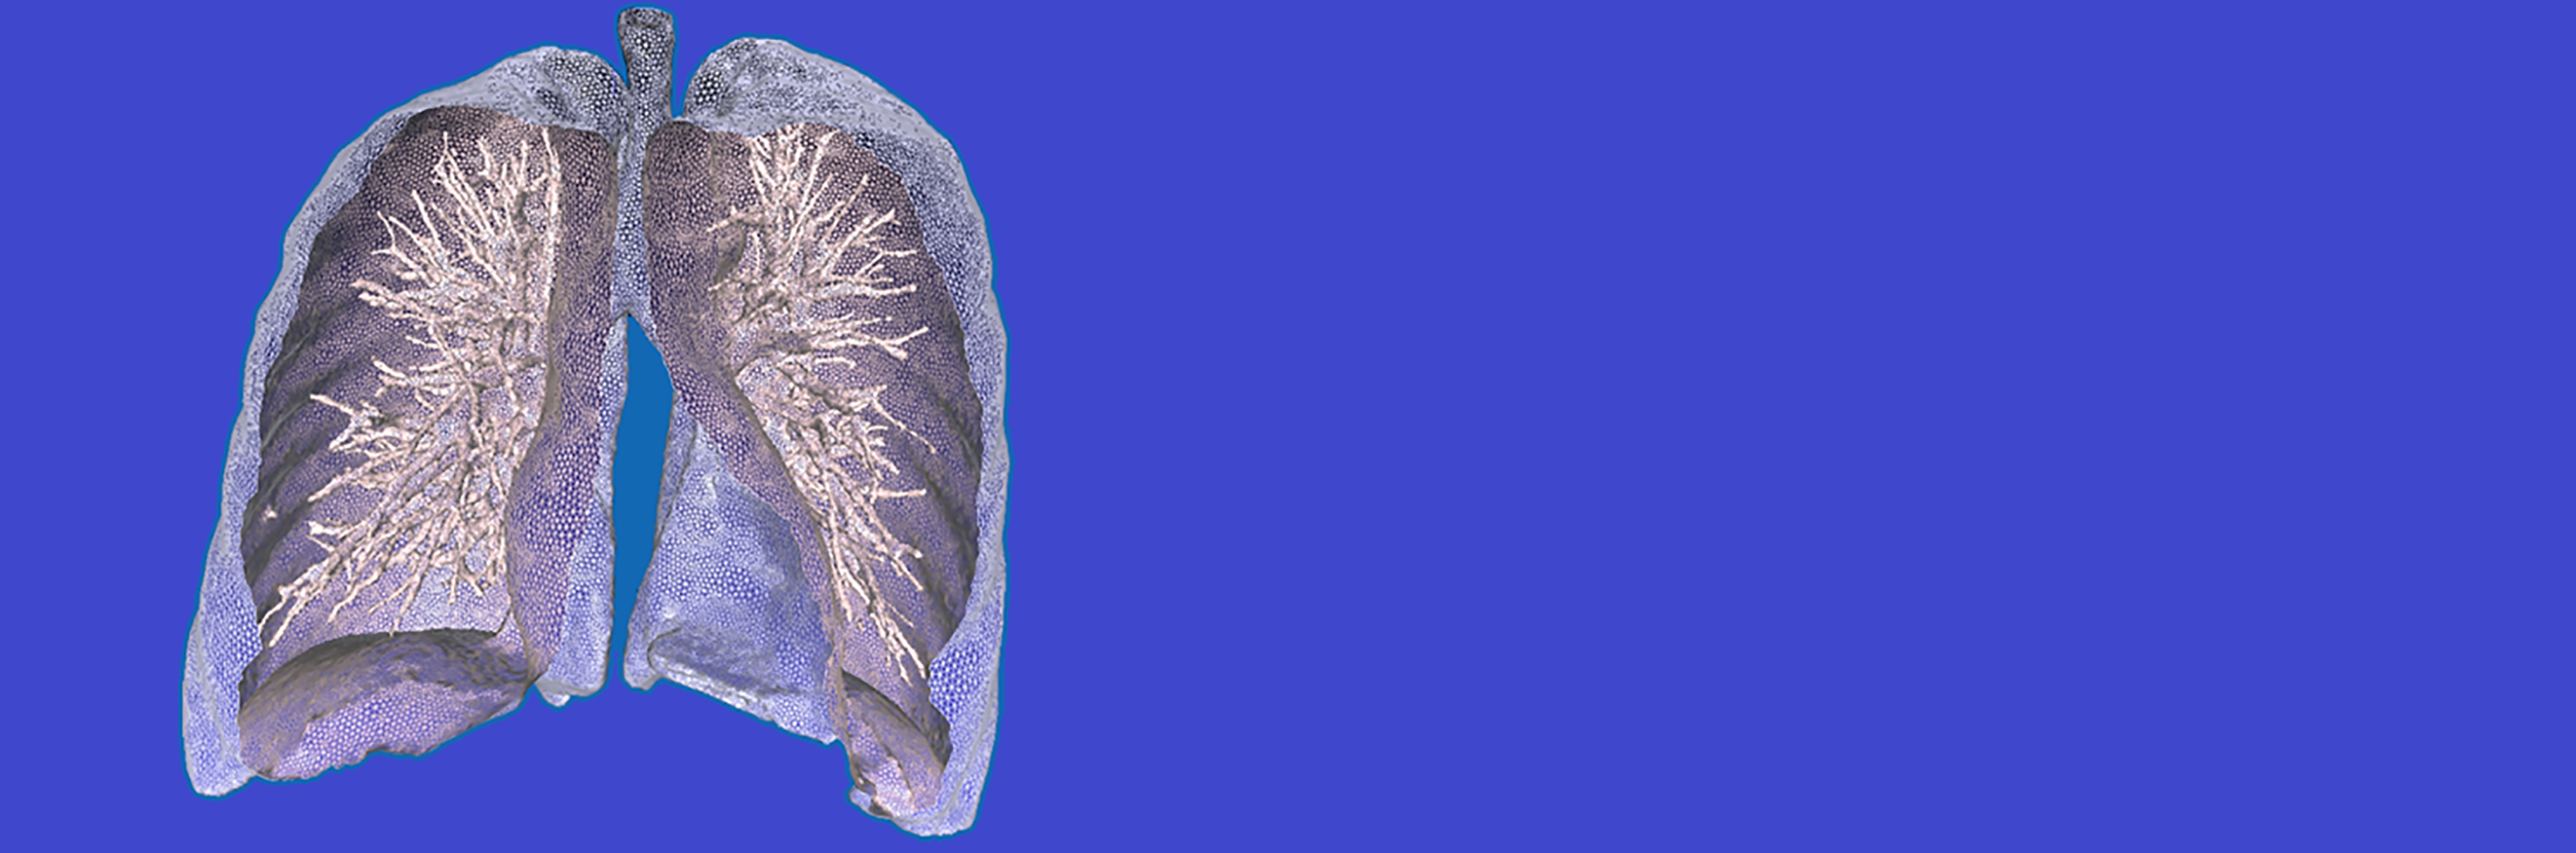

READ MOREFrom 3D scan data(CT/MRI/US) we can accurately segment area/volume of interest and output.

- Read MoreFrom 3D scan data(CT/MRI/US) we can accurately segment area/volume of interest and output a model for 3D printing or computational modelling and simulation.